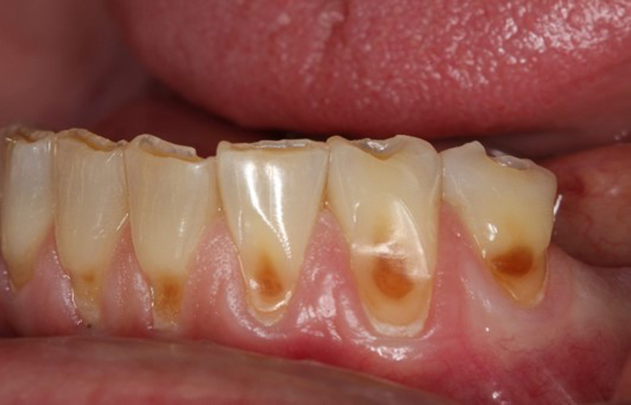

Concavities on the lingual surfaces of maxillary incisors (Figure 5) or occlusal surfaces of premolars and molars (Figure 6) with hollowed areas are signs of dental erosion that may be combined with attrition. Gastric acid is the most common cause of erosion on the lingual aspects of teeth. The most frequent etiology of gastric acid attack is the clinical diagnosis of GERD.13 Patients with anorexia nervosa and bulimia nervosa exhibit higher incidences of dental erosion.29 In Figure 7, a schematic drawing of an upper incisor demonstrates the sequence of loss of dentin and enamel on the lingual/palatal aspect. The direct contact of acid on the tooth structure is the main mechanism as the inorganic material dissolves, leading to a loss of surface hardness.13

Fig 3. Facial erosion of maxillary (Fig 2) and mandibular (Fig 3) anterior teeth.

Figure 3